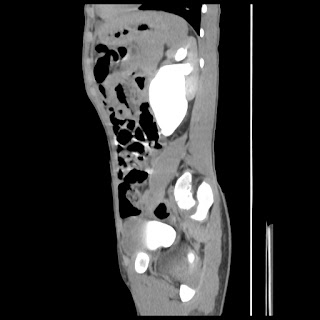

A 07 years old child with left side of abdomen pain

current CT images: